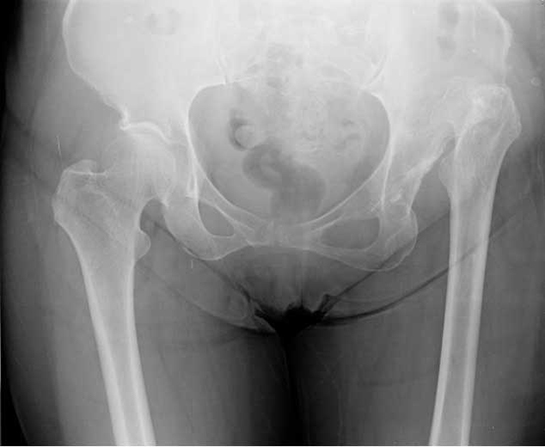

Kalça, insan vücudunun alt kısmında yer alan ve pelvis ile femur (uyluk kemiği) arasında bulunan karmaşık bir yapıdır. Kalça kemikleri, vücut ağırlığını taşımak ve hareket kabiliyetini sağlamak açısından son derece önemlidir. Bu makalede, kalça kemiklerinin adları, anatomik özellikleri ve işlevlerine dair detaylı bilgiler sunulacaktır.

1. Pelvis (Leğen Kemiği)

Pelvis, kalça kemiklerinin temel yapısını oluşturan ve birçok önemli kemiği barındıran bir yapıdır. Pelvis, üç ana bölümden oluşur:

• İlium (Kiriş Kemiği)

• Ischium (Oturma Kemiği)

• Pubis (Ön Kemiği)

Her bir bölüm, kalçanın çeşitli işlevlerini yerine getirmesinde önemli rol oynar ve bu kemiklerin her biri, pelvisin stabilitesini ve hareketliliğini artırır.

2. Femur (Uyluk Kemiği)

Femur, kalça bölgesinde bulunan en uzun ve en güçlü kemiktir. Femur başı, pelvisin asetabulum adı verilen boşluğuna oturur ve burada kalça eklemini oluşturur. Femur, aşağıdaki bölümlerden oluşur:

• Femur Başı

• Femur Boynu

• Femur Gövdesi

• Femur Şaftı

Femurun bu yapıları, hareketlilik ve stabilite sağlarken, aynı zamanda vücut ağırlığını taşımada da kritik bir rol oynar.

3. Asetabulum

Asetabulum, pelvisin lateral kısmında yer alan ve femur başının oturduğu yarım küre şeklindeki boşluktur. Bu yapı, kalça ekleminin başlıca hareket alanını belirler ve femurun hareket etmesine olanak tanır. Asetabulum, aşağıdaki kısımlardan oluşur:

• Asetabulum Dibi

• Asetabulum Kenarı

• Asetabulum Labrumu (Kıkırdak Doku)

Asetabulum, eklem stabilitesini artıran önemli bir yapı olarak öne çıkar.

4. Kalça Eklemi

Kalça eklemi, femur başı ile asetabulum arasında oluşan sferoidal (top şeklinde) bir eklemdir. Bu yapı, vücutta en hareketli eklemlerden biri olarak bilinir ve aşağıdaki hareketleri gerçekleştirebilir: